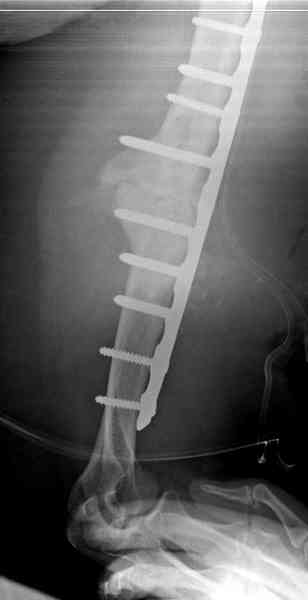

Как видно из выступлений коллег, способы фиксации

ложного сустава плеча могут быть различными, кто-то предпочитает аппаратом Илизарова (Соломин), пластинами (Волна) или интрамедуллярным гвоздем (Челноков).

Когда разбирался случай на сайте, и у нас была больная с похожей патологией, ложный сустав после поперечного перелома, леченного год назад где-то и кем-то в другом месте.

предложил Корнеев для лечения - применение анаболических стероидов - ретаболила, из-за его бессмысленности, также не согласились с его теорией, что любая операция заблокирует суставы, а наоборот, провели жесткую фиксацию пластиной для раннего восстановления.

Первичную пластину убрали недели 6 назад из переднего оригинального доступа, и из-за подозрительности тканей вокруг пластины, решили провести реконструкцию поэтапно.

Хотя сам не стороннник применения более массивных

имплантов для плеча, но для этого случая сделали

исключение. На снимке 4А диаметр мягких ткани около 20 см, при весе больной более 135 кг, и также выступление Андрея Волны подстегнуло к применению более массивной 4.5 мм локинг пластины.